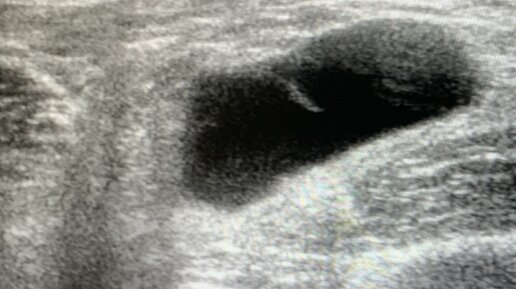

Гигромой называют доброкачественное образование, ограниченное капсулой, которое заполнено прозрачной серозной жидкостью. Чаще всего гигромы возникают в области сухожилий или суставов (лучезапястных или голеностопных), представляя собой опухоль круглой формы, которая покрыта неизмененной кожей. Врач травматолог-ортопед Андрей Викторович Баранов рассказал о методах лечения гигром в нашем учреждении. Несмотря на то, что гигрома является доброкачественной опухолью, она отличается высокой рецидивностью...